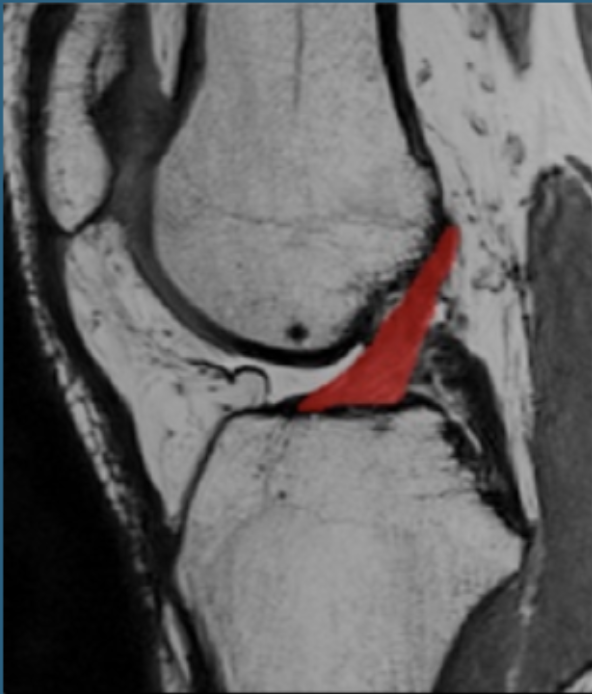

The relationship of ACL volume and T2 relaxation times to anterior knee laxity

A clinical knee arthrometer is commonly used to assess the integrity of the ACL for diagnostic and screening purposes. However, the structural properties that contribute to anterior knee laxity are not well understood. The results of this MRI-based study indicate that anterior knee laxity was largely predicted by the size of the ACL size and to a lesser extent ACL tissue quality, suggesting that those who have greater anterior knee laxity have smaller and structurally weaker ligaments. These findings support the use of cost-effective and clinically accessible measures of knee laxity to gain clinical insights into the structural quality of the ACL and potential injury risk.